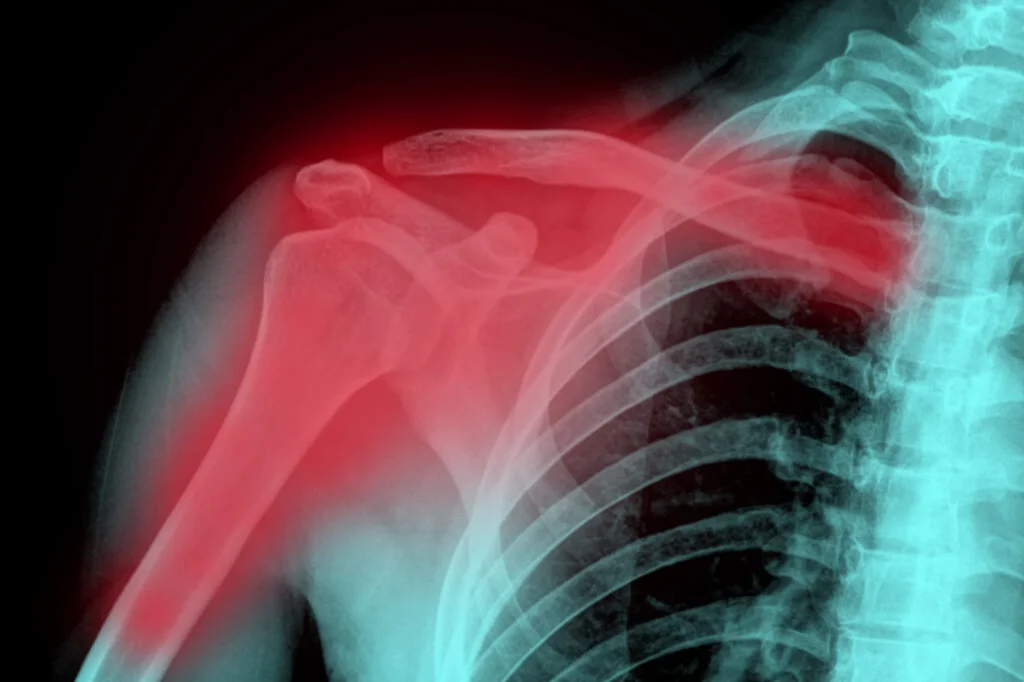

Diagnosis is the first step toward proper treatment. Your doctor will generally begin with a physical examination, checking your shoulder, arm, and hand for tenderness, swelling, bruising, and any signs of nerve or blood vessel damage.

Imaging studies may be used to confirm the fracture. X-rays are typically taken from several angles to clearly show the injury and determine the fracture type. If the break is complex, especially near the joint or if the bone is severely displaced, a CT scan may be ordered for a more detailed, three-dimensional view. This can be especially helpful when planning surgery.